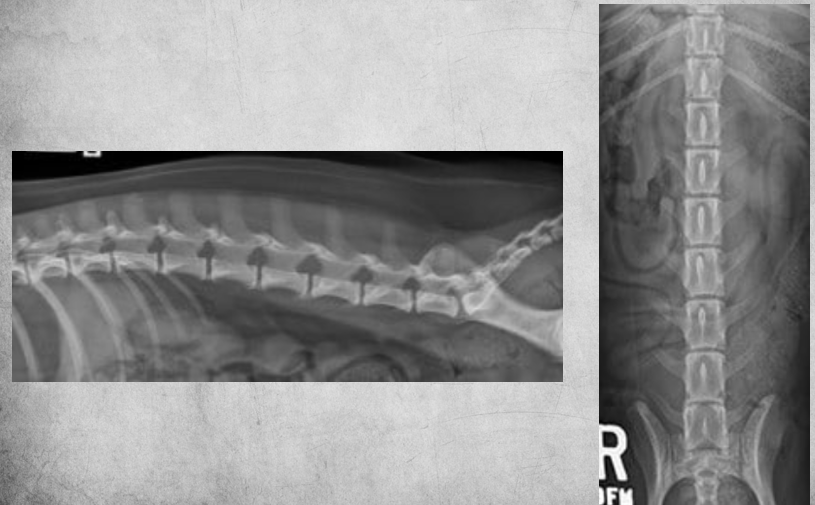

identify anomaly

Butterfly anomaly which is very specific to bulldog breeds (most have at least one if not more).

Vertebra is abnormally shaped like a butterfly.

Abnormality of ossification centers.

Two triangular units.

VD/DV views can catch it

Mostly asymptomatic.

Hemivertebra

Failure of formation of a part of the vertebral body. The vertebra is missing bone part ventrally or dorsally.

Seen in Lateral view, Wedge shape.

More common in brachys but found in others as well. Can cause pain.